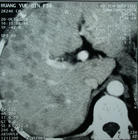

腸癌

直腸癌美國癌症協會估計美國在2000年新診斷出腸癌患將是93800名,其中47100人死亡。當按非常嚴格程式規律分裂的正常細胞失去控制時,各種類型的癌症都會發生,而環境因素肯定能引起癌症危險(例如吸菸、膳食和鍛鍊)。大多數癌也有基因基礎,確實幾百種基因和蛋白質包含在監視細胞分裂和DNA複製過程中,一種或多種基因或蛋白質的突變有時能導致失控癌細胞生長。